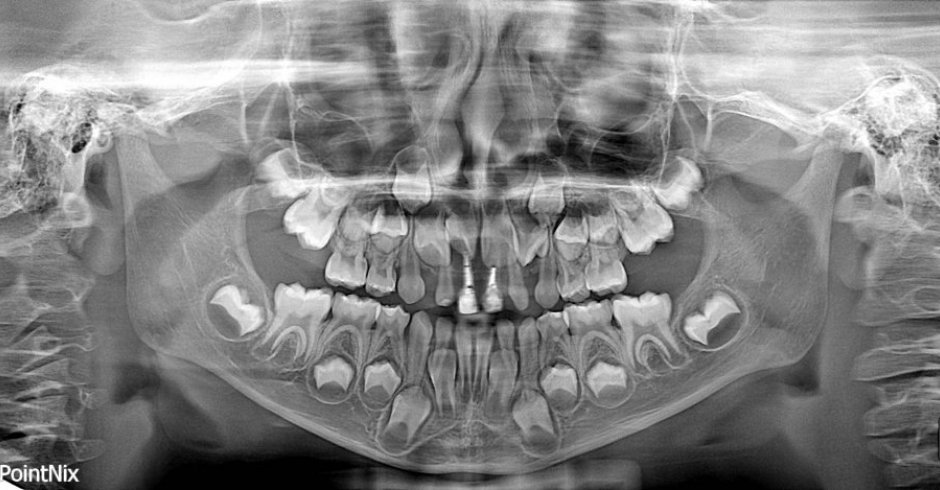

Técnica radiológica destinada a obtener una única imagen de las estructuras faciales que incluya las arcadas maxilar y mandibular, y sus estructuras de sostén.

Son una parte importante del tratamiento dental (tanto para adultos como para niños), ya que pueden detectar daño en los dientes y estructuras adyacentes  que no son visibles durante un examen visual de rutina.